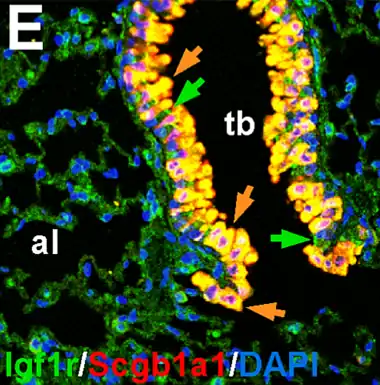

La señalización de factor de crecimiento similar a insulina (IGF en inglés), está involucrada en la homeostasis del pulmón humano. Por lo tanto, los IGF están implicados en la regeneración y reparación de heridas pulmonares en la edad adulta y, en consecuencia, se asocian con enfermedades respiratorias pulmonares relevantes como asma, fibrosis y cáncer.[12]

- ↑ a b c López I.P.; Piñeiro-Hermida S.; Pais R.S.; Torrens R.; Hoeflich A.; Pichel J.G. (2016). «Involvement of Igf1r in Bronchiolar Epithelial Regeneration: Role during Repair Kinetics after Selective Club Cell Ablation». PLoS ONE 11 (11): e0166388. doi:10.1371/journal.pone.0166388. Consultado el 6 de enero de 2021.